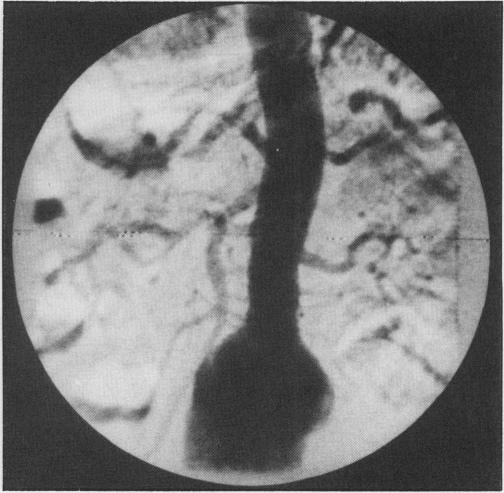

The treatment of abdominal aortic aneurysm has undergone dramatic changes over the last three decades. More sophisticated diagnostic techniques have allowed early elective repair to be carried out. Improvement has resulted in both morbidity and mortality rates. Investigations such as ultrasound, computerized tomographic scanning and arteriography allow easy confirmation of the diagnosis of aortic aneurysms and permit a better assessment of the extent prior to surgical intervention. Improvement in the pre-operative management, particularly in relation to cardiac, renal, and pulmonary disease, has led to greatly improved results. The most important change in surgical technique has been repair of the aneurysm rather than resection. Combined with better post-operative intensive care units, this development has contributed to the improved morbidity and mortality rates. Although the complication rate of elective repair is low, the major cause of death remains myocardial infarction. As a result of all these improvements, indication for repair of abdominal aortic aneurysms has been extended to patients over the age of 80. Following surgical repair, most patients can be expected to return to normal lifestyles and lifespans.

在过去的三十年中,腹主动脉瘤的治疗发生了巨大的变化。更复杂的诊断技术使得早期选择性修复得以进行。这导致发病率和死亡率都有所降低。超声、计算机断层扫描和血管造影等检查可以轻松确认主动脉瘤的诊断,并在手术干预前更好地评估其范围。术前管理的改善,特别是在心脏、肾脏和肺部疾病方面,导致了结果的显著改善。手术技术最重要的变化是修复动脉瘤而不是切除。与更好的术后重症监护病房相结合,这一发展有助于降低发病率和死亡率。尽管选择性修复的并发症发生率较低,但主要的死亡原因仍然是心肌梗死。由于所有这些改进,腹主动脉瘤修复的适应证已扩展到 80 岁以上的患者。手术后,大多数患者可以恢复正常的生活方式和寿命。

The place of abdominal aortography in abdominal aortic aneurysm resection.腹主动脉造影在腹主动脉瘤切除术中的地位。

Arch Surg. 1983 Sep;118(9):1029-34. doi: 10.1001/archsurg.1983.01390090019004.